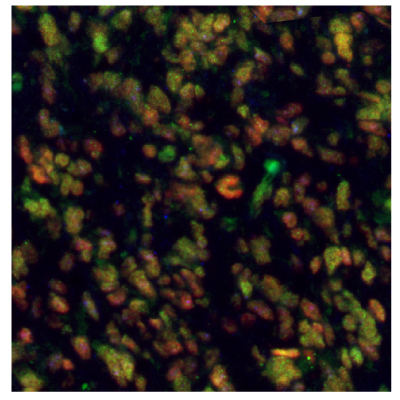

Figure 8 shows immunostainings of EZH2, PARP1, and ALDH1A3 expression in various sample types.

Figure 8A.Multiplexed IHC-IF staining of human glioblastoma using the Anti-EZH2 monoclonal (nuclear, in green), the Anti-PARP1 monoclonal (nuclear, in red), and the Anti-ALDH1A3 monoclonal (cytoplasmic, in blue) antibodies.

Figure 8B.Multiplexed IHC-IF staining of human astrocytoma samples using the Anti-EZH2 monoclonal (nuclear, in green), the Anti-PARP1 monoclonal (nuclear, in red), and the Anti-ALDH1A3 monoclonal (cytoplasmic, in blue) antibodies.

Figure 8C.Multiplexed IHC-IF staining of human oligodendrocytoma samples using the Anti-EZH2 monoclonal (nuclear, in green), the Anti-PARP1 monoclonal (nuclear, in red), and the Anti-ALDH1A3 monoclonal (cytoplasmic, in blue) antibodies.

Figure 8D.Multiplexed IHC-IF staining of human normal cortex samples using the Anti-EZH2 monoclonal (nuclear, in green), the Anti-PARP1 monoclonal (nuclear, in red), and the Anti-ALDH1A3 monoclonal (cytoplasmic, in blue) antibodies.